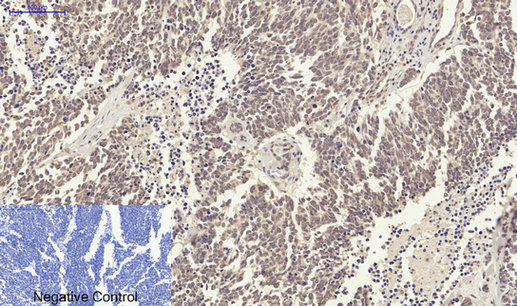

ARG66190 anti-Smad 2 antibody IHC-P image

Immunohistochemistry: Paraffin-embedded Human uterus cancer tissue stained with ARG66190 anti-Smad 2 antibody at 1:200 dilution (4°C, overnight). Antigen Retrieval: Boil tissue section in Sodium citrate buffer (pH 6.0) for 20 min.

Negative control was used by secondary antibody only.